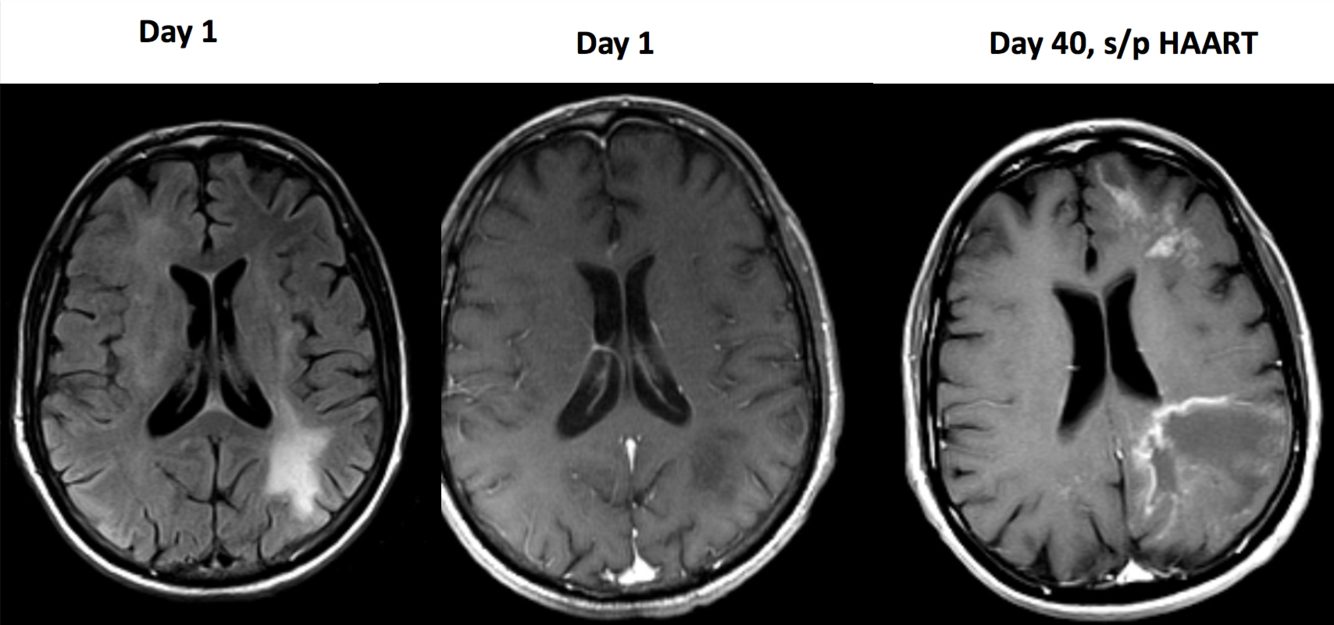

45 year-old HIV patient with confusion and lethargy after starting HAART.

PML with IRIS (immune reconstitution inflammatory syndrome)